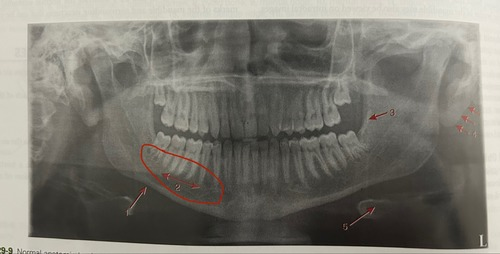

Lingual foramen surrounded by genial tubercles

External oblique ridge

Mental foramen

Mental fossa

Mental ridge (premolar & incisor region)

Inferior border of mandible